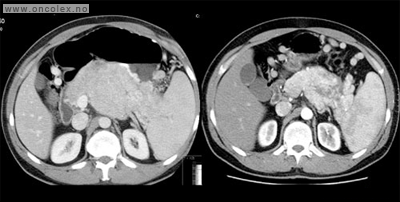

Bildeeksempler